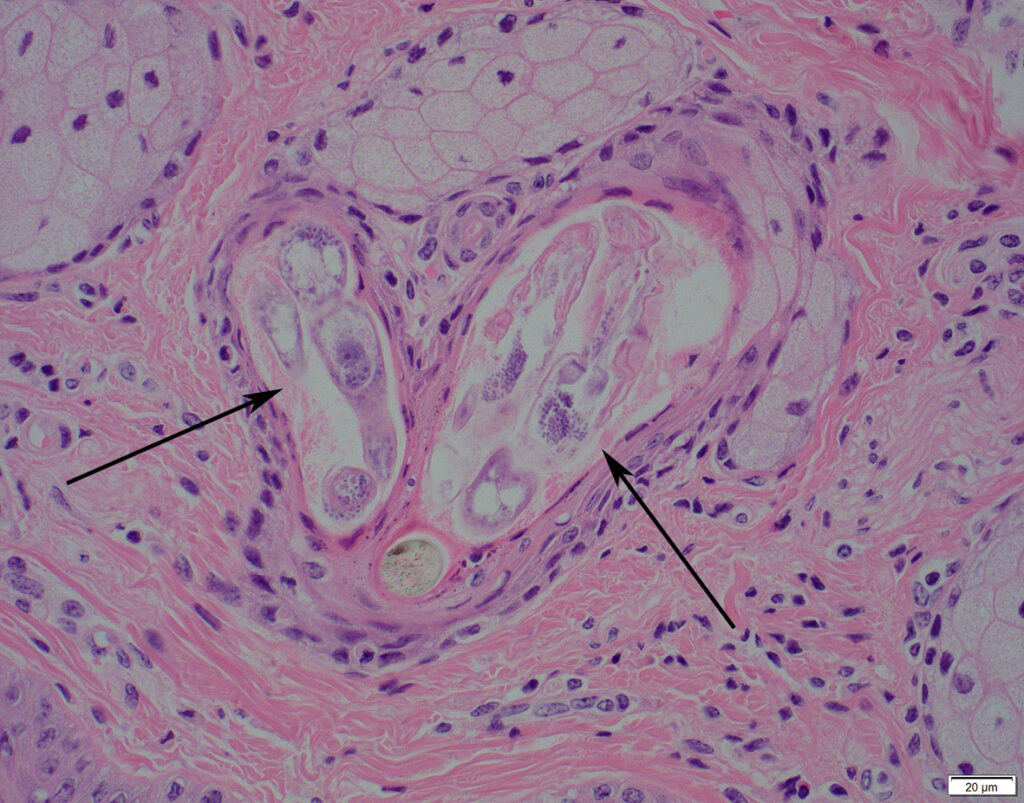

Het onderzoek toonde aan dat de kaalheid bij beide dieren door demodex-mijten was veroorzaakt. Kaalheid die door demodex-mijten wordt veroorzaakt, wordt demodicose genoemd en kan lokaal of over bijna de gehele vacht verspreid voorkomen.

Mijten vormen normaal gesproken geen probleem voor de gastheer, maar als het evenwicht tussen gastheer en mijt om de een of andere reden is verstoord, kunnen de aantallen mijten sterk toenemen en kaalheid veroorzaken. Hoe het mechanisme precies werkt is nog niet helemaal duidelijk, maar men weet dat de grotere aantallen mijten zwelling van de talgklieren en haarzakjes veroorzaken, waardoor het haar uitvalt. Een ander mogelijk effect is dat de mijten zorgen voor een vertraging van de haargroei. In de aangetaste haarzakjes, kan vervolgens een bacteriële infectie optreden en/of kunnen zweren ontstaan.